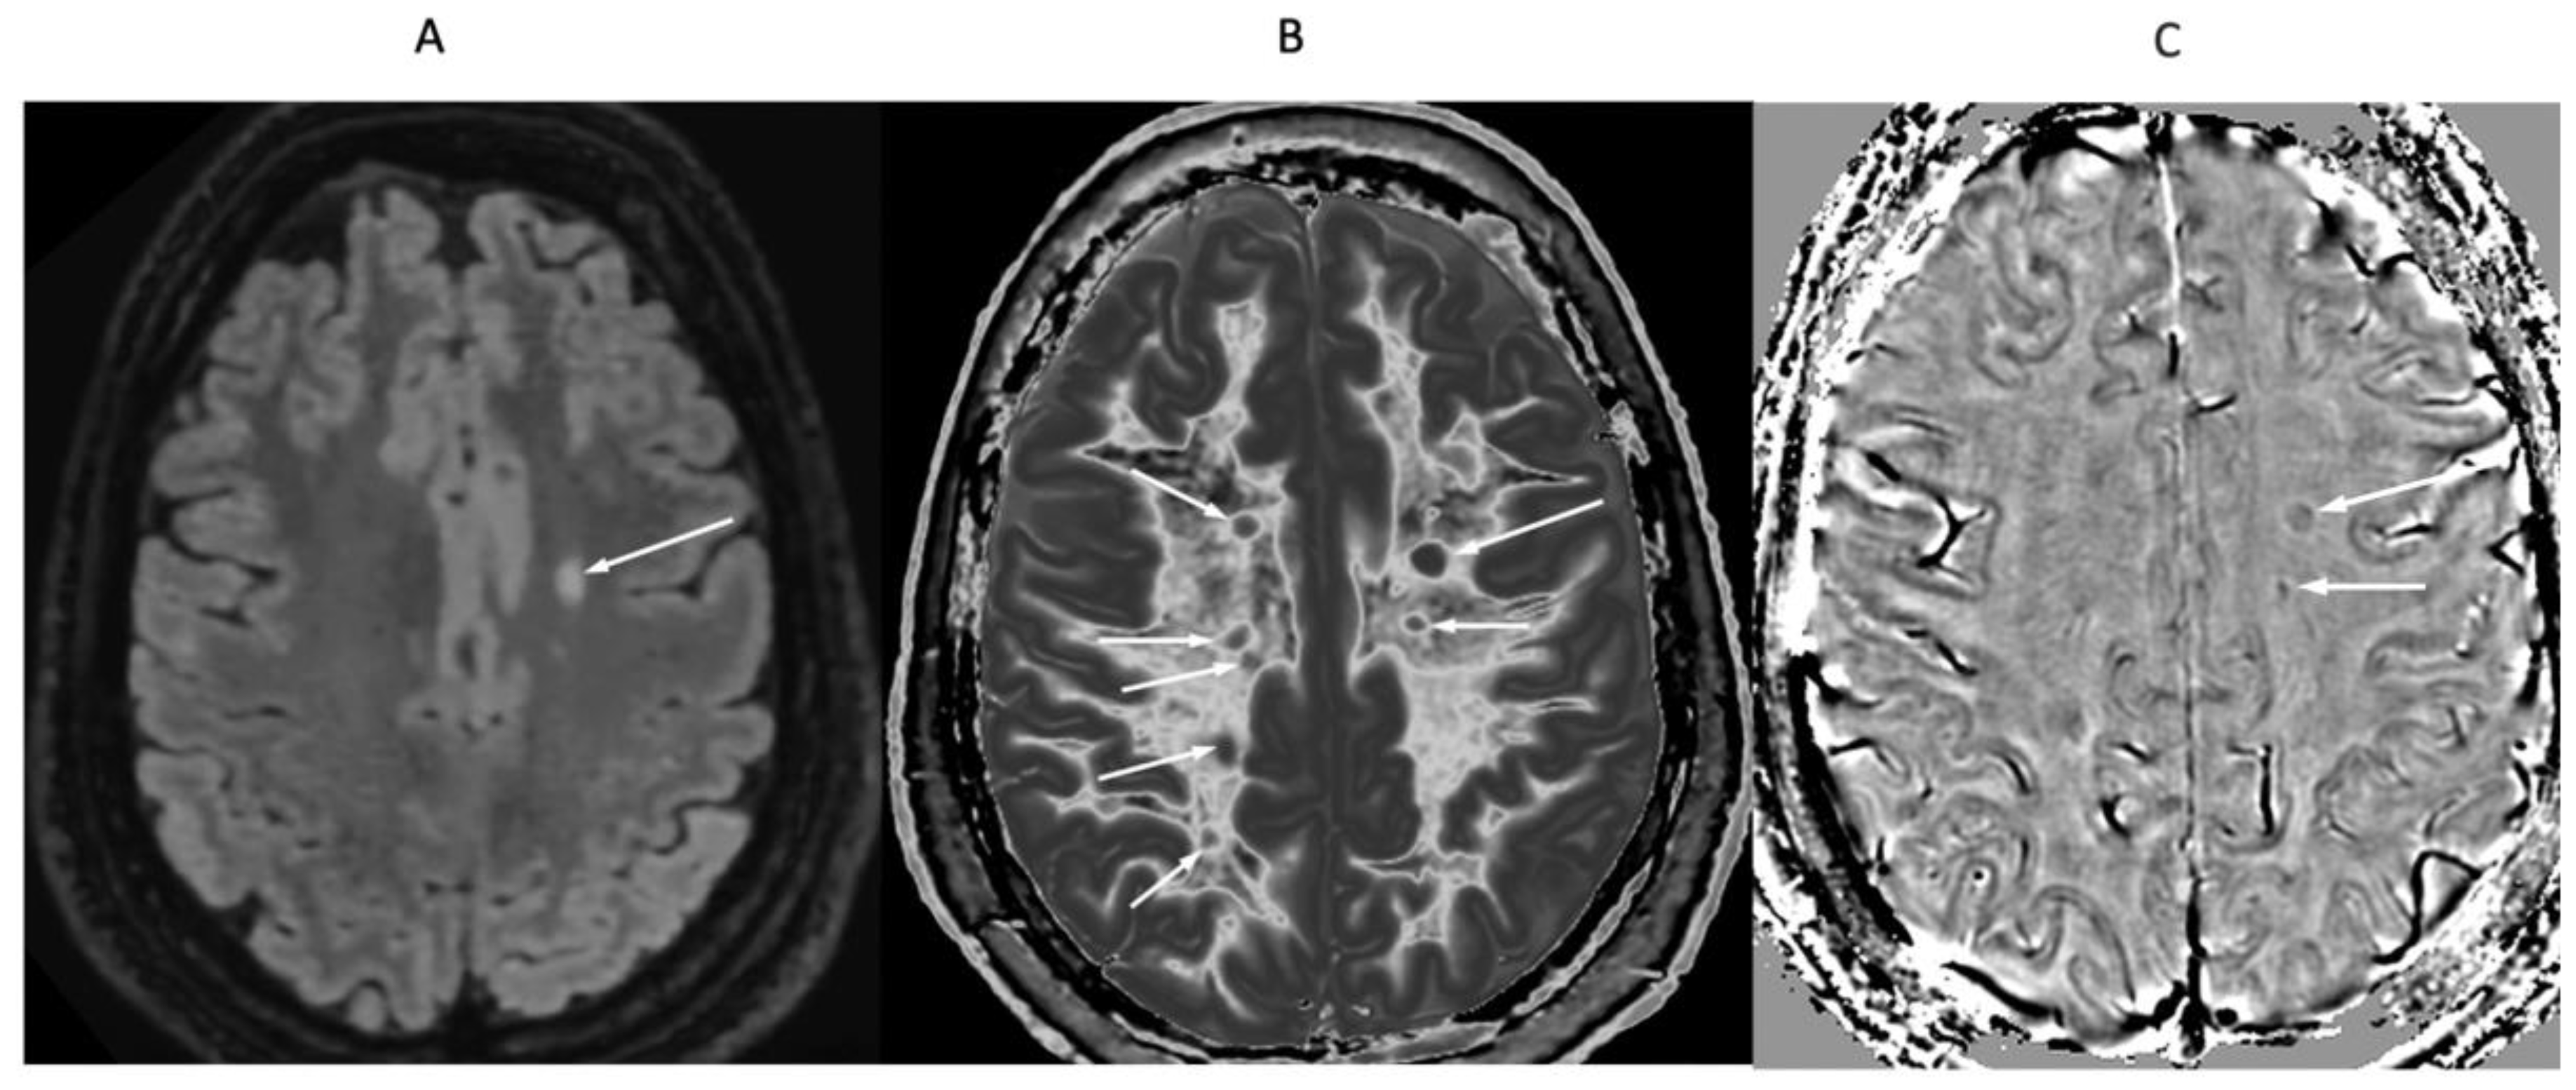

In a 41-year-old female patient with MS, the dSIR image (

Figure 23A) shows a blurred leukocortical lesion in the right medial frontal region with no evidence of a white matter-gray matter boundary within it. The matched lSIR image (

Figure 23B) shows a disrupted high signal boundary between white matter and gray matter within the lesion. Profiles (plots of signal against position in mm) through the lesion at the level shown by the arrows for the dSIR (blue) and lSIR (orange) images shows a higher signal and steeper slope for the lSIR image (

Figure 23C). The spatial resolution of the contrast i.e., change in signal with change in position is generally higher on the lSIR image.

Figure 23.

41-year-old female patient with MS. A leukocortical lesion in the right medial frontal region is shown on the narrow mD dSIR (T1-BLAIR) image (A) and a matching lSIR image (B) (arrows). There are also left to right profiles with signal plotted against position (in mm) for the dSIR (blue) and lSIR (orange) images (C) at the level of the horizontal arrows shown in (A) and (B). No boundary between white matter and gray matter is seen within the lesion in (A). A disrupted high signal boundary between white matter and gray matter is seen in the lesion in (B). The lSIR profile (orange) has higher signal and steeper slopes than the dSIR profile (blue) in (C). The difference in signal (or contrast) achieved for the same change in position is generally greater with the lSIR filter i.e., the contrast shown on the lSIR image generally has a higher spatial resolution.